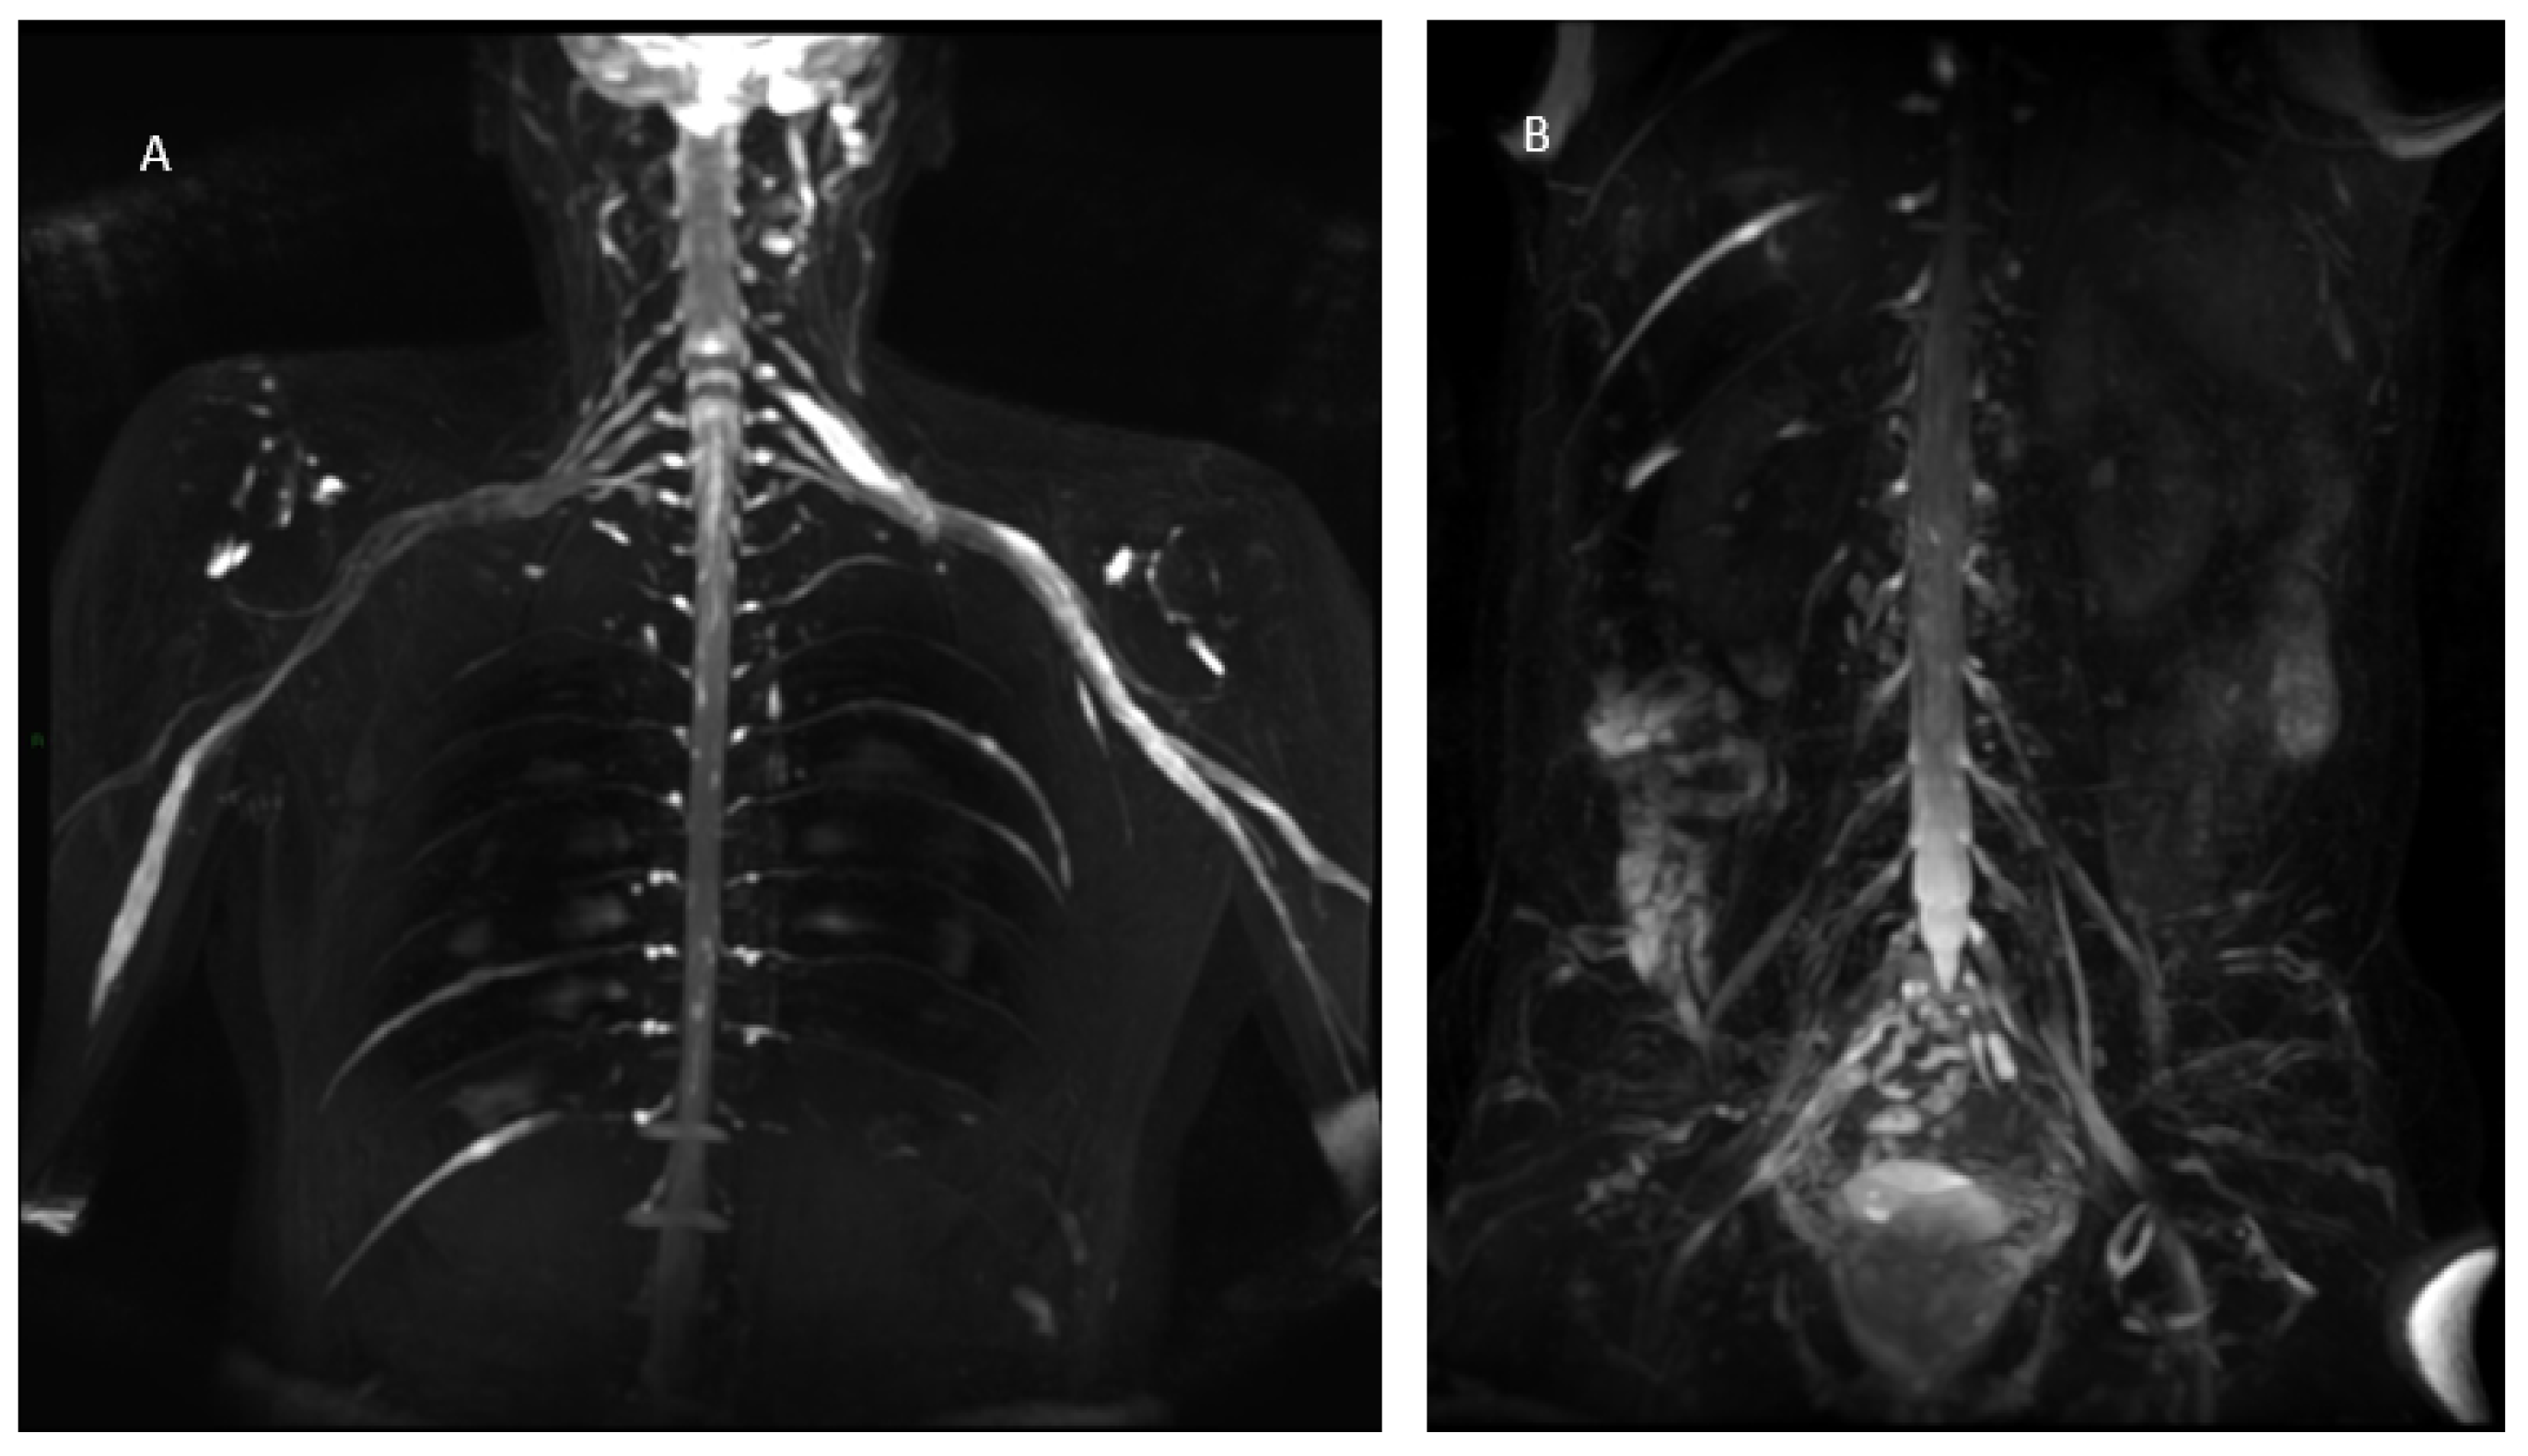

Figure 8.

MIP (Maximum Intensity Projection) reconstructions of the 3D cube nerve-MR sequence of the lumbosacral plexus documented a moderate and diffuse increase in thickness and signal intensity on T2W images of the lumbar and sacral roots; the left S1root (arrows) appears to be pathological (thickened and markedly hyperintense in T2w). Transverse diameter S1 roots (n.v. * 5.27 ± 0.53) left 8.4 mm; right 8.2 mm). * Normal values (n.v.) according to the recent study of Su X et al. [20].